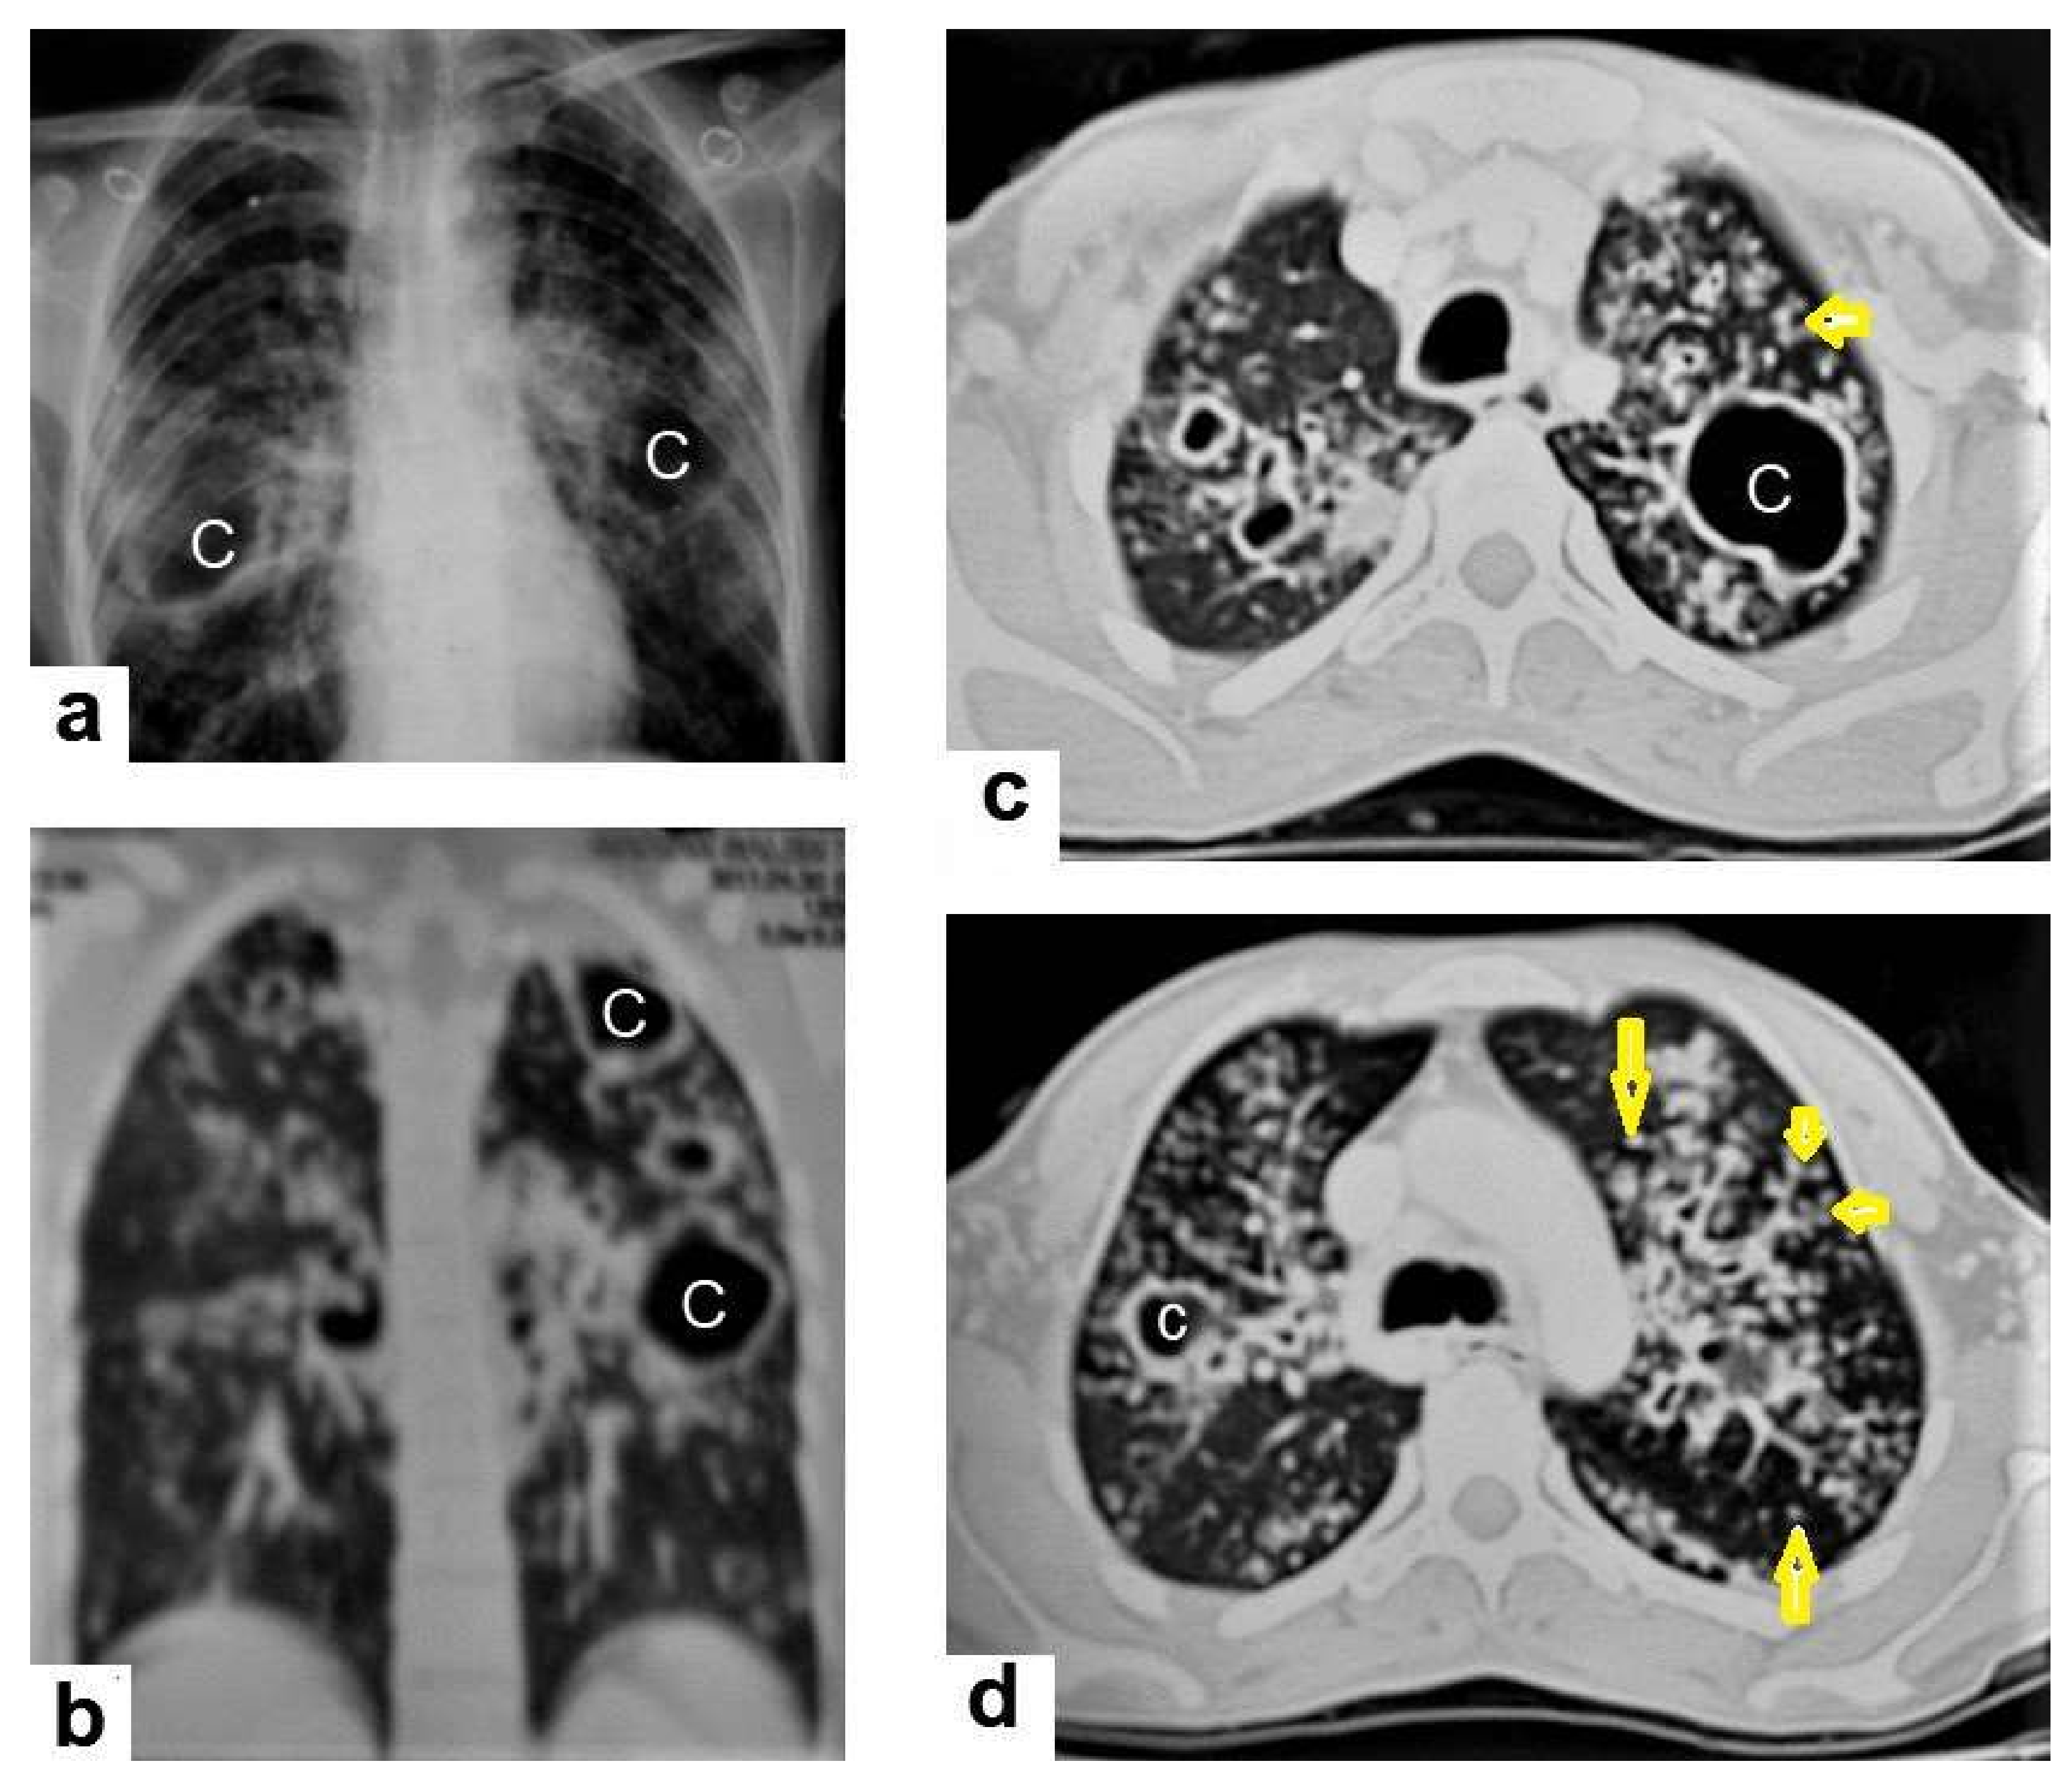

• Cavitation (Figure 3 and Figure 4) is a common finding in postprimary TB, and it is characterized as being several centimeters in size with thick irregular walls. Cavities are often seen within consolidation and may persist after treatment predisposing to a bacterial or fungal superinfection or adjacent vascular erosion causing hemoptysis [1,10]. In postprimary TB, both consolidation and cavitation have a predilection for the apical and posterior segments of the upper lobes and the upper segments of the lower lobes [1,14]. This predilection of TB is attributed to the relative over-ventilation, high oxygen tension, and delayed lymphatic clearance in these regions [16]. Thick wall cavities are an important differential diagnosis of a pulmonary abscess, septic emboli, aspergilloma, granulomatosis with polyangitis (Wegener’s granulomatosis), lung malignancy, and others [17].

• Centrilobular nodules (Figure 4 and Figure 5) occur due to the communication of active TB with the bronchial tree resulting in endobronchial spread. It occurs in most cases of active TB. It appears as centrilobular nodules and a tree-in-bud sign on CT images [1,10]. The tree-in-bud pattern is seen on high-resolution CT images as 2–4 mm centrilobular nodules of soft tissue density that are connected to multiple branching linear structures of the similar caliber, arising from a single stalk. It commonly occurs in the endobronchial spread of TB and is highly suggestive of active TB. However, a tree-in-bud is a CT manifestation of the diverse entities of lung diseases, including TB, cytomegalovirus, respiratory syncytial virus, obliterative bronchiolitis, diffuse panbronchiolitis, cystic fibrosis, airway-invasive aspergillosis, allergic bronchopulmonary aspergillosis, and pulmonary metastasis [18].

• Miliary TB (Figure 6 and Figure 7) appears as innumerable small (1–3 mm) granulomas with random distribution in the lungs and other organs with a predominance to the lung bases due to the gravity-dependent high blood flow. It occurs due to the hematogenous dissemination of mycobacterium tuberculosis bacilli, especially in immunocompromised patients and children [1,13]. Miliary TB is a significant differential diagnosis of pulmonary metastasis from thyroid cancer or others, even in children [19].

Figure 4. Reactivated TB in a 34-year-old women. (a) Chest radiograph shows extensive reticular shadowing and multiple cavitary lesions in both lungs. (b) Coronal reconstruction CT shows multiple cavitary lesions (c) in both lungs, the large two in the posterior segment of the upper lobe, and in the apical segment of the lower lobe of the left lung. (c,d) Axial CT images of the lung show multiple cavitary lesion, the largest in the posterior segment of the left upper lobe, with multiple centrilobular (long arrows) and tree-in-bud (short arrows) appearance.